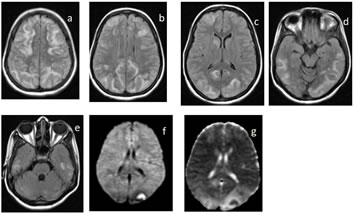

Figure 1: Posterior reversible encephalopathy syndrome (PRES) in a 28yrs female who presented with generalized tonic clonic seizures on 7th post operative day of emergency LSCS. MRI showed relatively symmetrical cortical and subcortical edema on FLAIR in typical locations involving bilateral posterior parietal and occipital lobes, but no diffusion abnormalities (not shown)